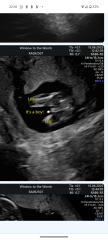

How accurate is this scan 15+2

I'm in actually disbelief and just looking for some reassurance that this is a little boy. I know 15+2 is still super early but the sonographer took ages to find out and didn't seem too confident when she told me.

Absolutely a boy! I had a gender scan with my first at around 15w-ish and by then it was accurate. I'm sure some private scan companies offer gender scans as early as 14w!